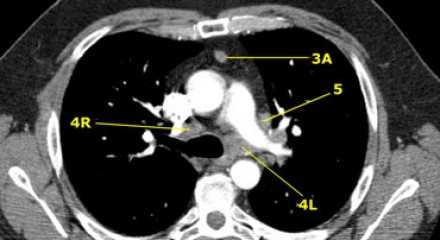

На левом изображении над уровнем легочного ствола представлены нижние паратрахеальные узлы слева и справа, так же здесь представлены узлы 3 и 5 групп.

Изображение слева выше уровня карины. Слева от трахеи 4L узлы. Обратите внимание что они расположены между легочным стволом и аортой, но не в аортопульмональном окне, потому что они лежат медиальнее артериальной связки. Лимфатические узлы латеральнее легочного ствола относятся к 5 группе.

- 5. Субаортальные лимфатические узлы

- Субаортальное или аортопульмональное окно расположено кнаружи от артериальной связки и проксимальнее первой ветви левой легочной артерии и лежит в пределах медиастинальной плевры.